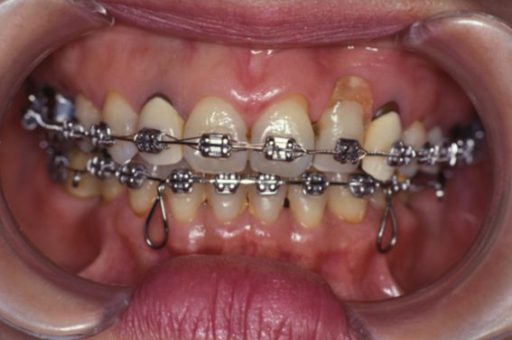

歯周病に罹患した患者さんのインプラント治療の症例①(うえだ歯科)

上田大介(うえだ歯科)

症例詳細

| 主訴 | 全顎治療希望、奥の歯茎から血が出る、綺麗で噛めるようになりたい |

| 治療内容 | 全顎的に歯周病、歯列不正が認められるため、歯周外科を含む歯周治療、矯正治療、インプラント治療、セラミックによる補綴治療後メインテナンスに移行 |

| 治療費 | 2,930,000円(税込)(インプラントすべて含む) |

| 治療期間 | 2年6ヶ月 |

| 治療回数 | 96回 |

| 想定されたリスク | 歯周病の再発、食いしばり(パラファンクション)によるセラミックの破折、歯の破折 |